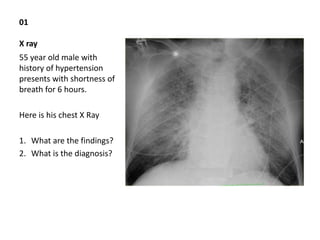

This document contains multiple patient case summaries and medical images/reports with questions related to diagnosis and management. Some key cases include: - A 55-year-old male presenting with shortness of breath, whose chest X-ray shows cardiomegaly and upper lobe diversion. - A 35-year-old male with progressive shortness of breath and cough presenting with bilateral hilar lymphadenopathy on chest X-ray, leading to a diagnosis of sarcoidosis. - An ECG showing findings of atrial fibrillation in a 35-year-old female presenting with palpitations. - A CT scan of a 30-year-old IV drug user presenting with fever

Final year ospe

- 1. 01 X ray 55 year old male with history of hypertension presents with shortness of breath for 6 hours. Here is his chest X Ray 1. What are the findings? 2. What is the diagnosis?

- 2. 01 Key Findings: Cardiomegaly, Upper lobe diversion